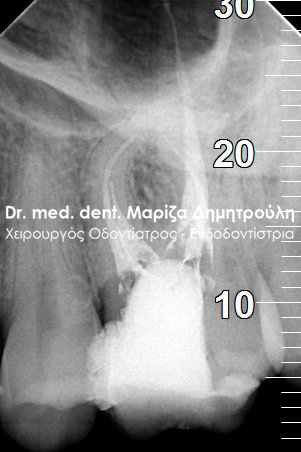

Clinical photo of root canal filling

AFTER